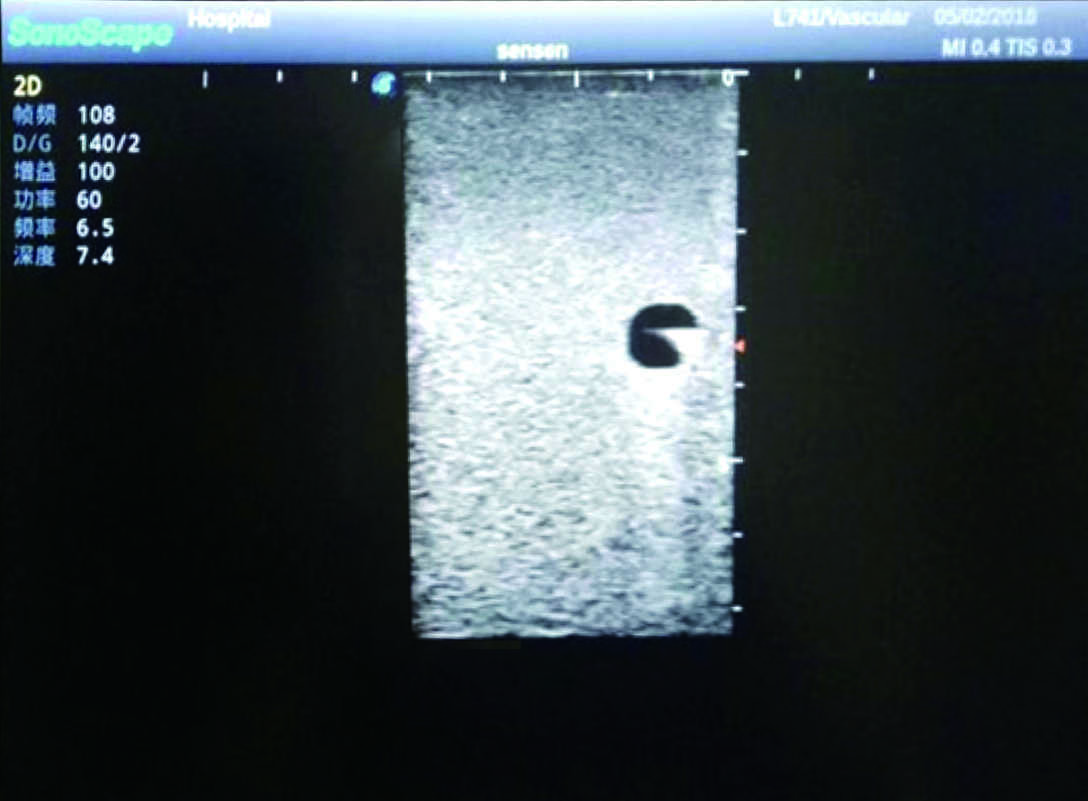

PICC Ultrasound Training Model

Model TYE1510.1

It is a model covering up from lobulus auriculae plane to the umbilical plane, and it has anatomical structures like clavicle, rib, sternocleidomastoid, jugular vein and basilic vein.

1)   Made of high molecular polymer ultrasound material, close to the real skin

2)   It can be used by real ultrasound machines

3)   Clear and real images of the tissues and organs (basilic vein and superior vena cava)